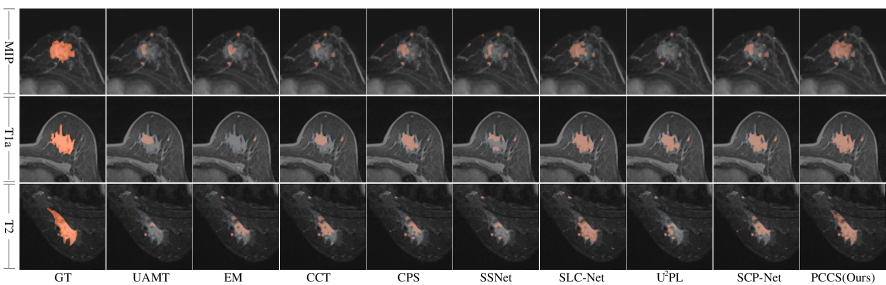

Results of Comparison on Visualization. Fig. 5 showcases the visualization outcomes of various methods applied to the BUSI dataset when employing 20% annotated images and 80% unannotated images. A comprehensive comparative analysis is conducted among nine methods: UAMT, EM, CCT, CPS, SSNet, SCL-Net, U2PL, SCP-Net, and PCCS. The leftmost column illustrates the Ground Truth (referred to as GT), serving as a reference for comparison. Subsequently, the first, second, and third rows present the segmentation visual results for MIP, T1a, and T2, respectively. Observing the visualizations, it becomes apparent that the boundaries of lesion areas exhibit irregular shapes, and there are also some spot-like signals present in non-lesion areas. These irregular shapes and spot-like noise present challenges for precise segmentation. While existing semi-supervised methods excel at learning features with regular shapes within lesion areas, they often struggle to accurately segment areas with irregular boundaries. In contrast, PCCS effectively establishes relationships between uncertainty-guided boundary prototypes, facilitating the learning of more discriminative features and mitigating noise caused by spot-like signals. Consequently, the segmentation results produced by PCCS across the three modalities demonstrate greater consistency with the true boundaries of the ground truth, exhibiting fewer missing and unexpected regions.